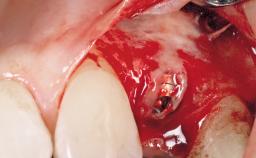

Immediate Flapless Placement of an Implant in a Maxillary Left Central Incisor Site

A 29-year-old female patient presented for treatment to replace the upper left central incisor tooth with an implant- supported restoration. The tooth had been intermittently symptomatic for the previous 12 months. The tooth had originally suffered trauma about 15 years previously. Several endodontic treatments had been performed, including an apicectomy procedure to retain the tooth. The patient was healthy and a non-smoker. She had reasonable expectations in regard to esthetic outcomes and the risk of marginal tissue recession following treatment. At medium smile, the gingival margins of the upper teeth were visible, with a display of 3 to 4 mm of the gingival margins. Gingival recession of tooth 21 and a discrepancy in the gingival levels between teeth 11 and 21 was observable during normal speech and smile.

| Placement Protocol | Immediate implant placement |

| Socket Morphology | Single-root socket |

| Socket Integrity | Damage to one or more bone walls |

| Bone Volume | Damage to one or more socket walls |